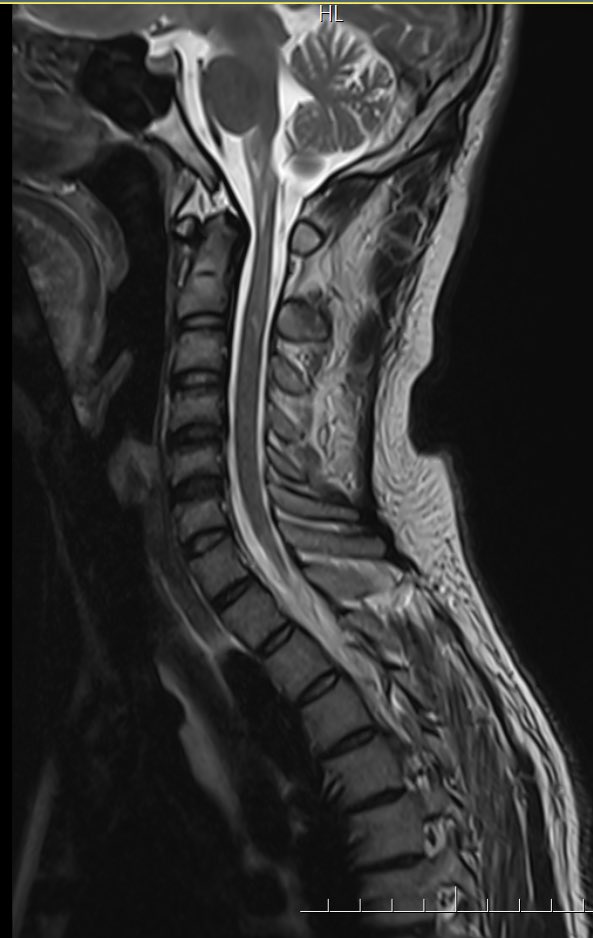

@nodisability I think it is the symmetry on MRI + location+ presentation + family history

@bobvarkey What's classical to think GFAP mutation in MRI here? Owls eye?

@bobvarkey Ooh this looked like olivo ponto cerebellar degeneration. Thanks for the education

Clinical exome sequencing shows GFAP mutation consistent with

🧠 Alexander Disease

Final Dx - Alexander Disease Bulbospinal variant

🔬 Pathophysiology

• Cause: Gain-of-function mutations in GFAP gene (chromosome 17q21)

• Hallmark: Rosenthal fibers — protein aggregates in astrocytes containing GFAP, heat shock proteins, ubiquitin

• Mechanism: Abnormal GFAP crosslinking via oxidation and ubiquitination (Lin et al., 2024)

👤 Clinical Phenotypes

Revised Classification (2011):

• Type I: Cerebral, early onset, median survival ~14 years

• Type II: Bulbospinal, later onset, median survival ~25 years

🩺 Diagnosis

• MRI: 4 of 5 criteria needed (frontal WM predominance, periventricular rim, basal ganglia abnormalities, brainstem involvement, contrast enhancement)

• Genetic testing: Confirms diagnosis